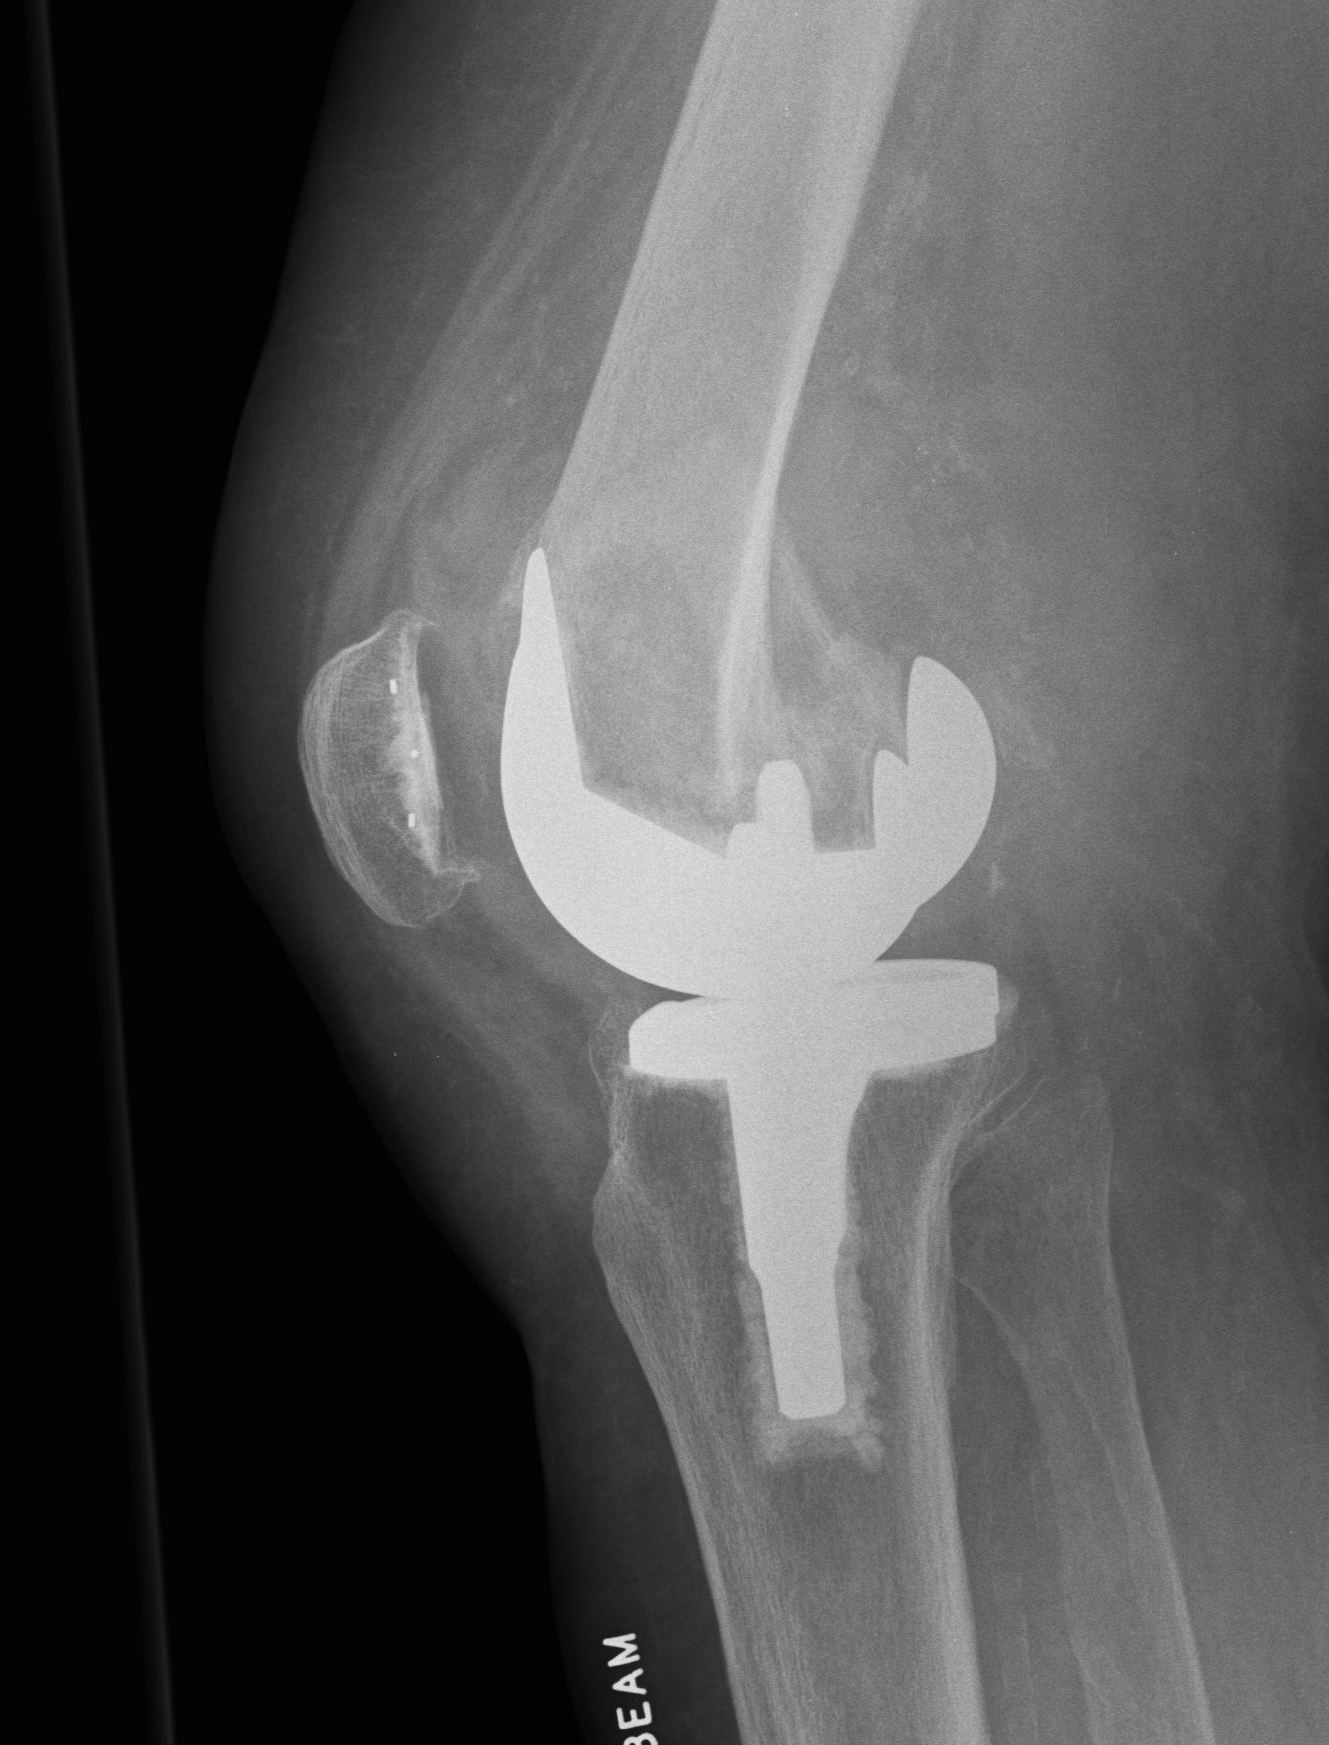

4.  Revision TKR

Indications

- very distal fracture

- insufficient bone stock

- loose prosthesis

Components

- stemmed, constrained implant

- tumour prosthesis

TKR Periprosthetic Fracture APTKR Periprosthetic Fracture LateralTKR Periprosthetic Fracture Revision APTKR Periprosthetic Fracture Revision Lateral